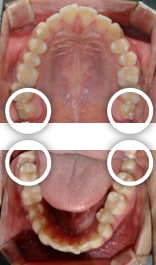

사랑니는 좌우 위아래로 4개가 있지만 간혹 사람에 따라 1개~3개만 발생하는 경우도 드물게 나타나며, 현대에 이르러서는 사랑니가 애초에 없는 사람도 많은 편입니다.

하지만, 사람에 따라서는 공간이 충분해서 사랑니가 반듯하게 나고, 씹는 기능까지 보유한 경우도 더러 있습니다.

이 경우에는 남들보다 한 개 더 큰 어금니를 보유해 총 3개의 큰 어금니로 더욱 튼튼한 환경을 가지게 된 것이므로, 사랑니를 소중히 여기며 평생 잘 사용해야 합니다.